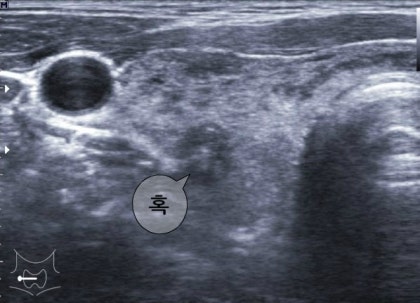

수치가 높게 나와서 정밀검사 진행했어요~

THS 정상 수치가 0.35~5.50인데,

29.6 나왔습니다.

인공지능 기반

초고해상도 초음파란

괜히 더 잘 봐줄 것 같은 느낌.